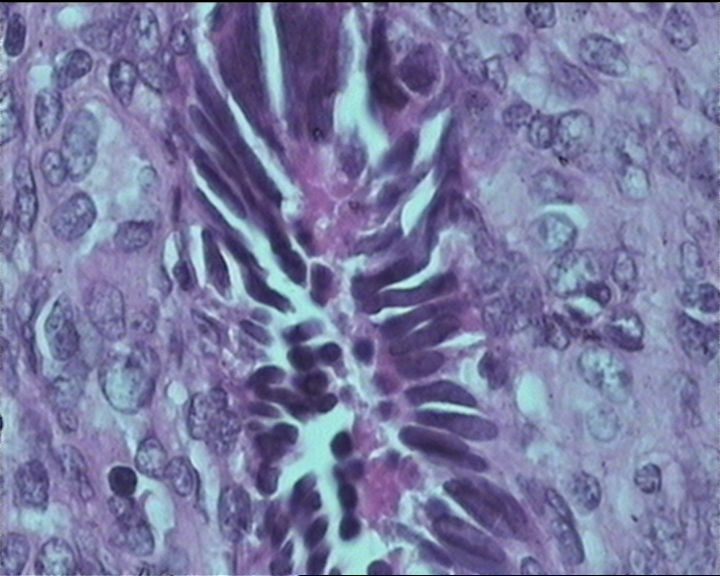

54岁女性,临床“宫颈息肉”送检;巨检:组织一块1。5*1CM,灰红。

输卵管粘膜化生

It is benign. Benign endocervical polyp with tubal metaplasia.

细胞及腺体均有异形,图6、11、16象有纤维间质反应,考虑高级别上皮内瘤变/原位癌,腺癌不能除外。

Sternberg病理学上诊断宫颈原位腺癌的标准是腺体的上皮去粘液分化,呈乳头状或筛网状增生,核分裂易见,这例显然达不到此标准。此例还是归入到腺上皮不典型增生为好。

杨老师说它是良性的,是个颈管内膜息肉伴输卵管上皮化生,良性